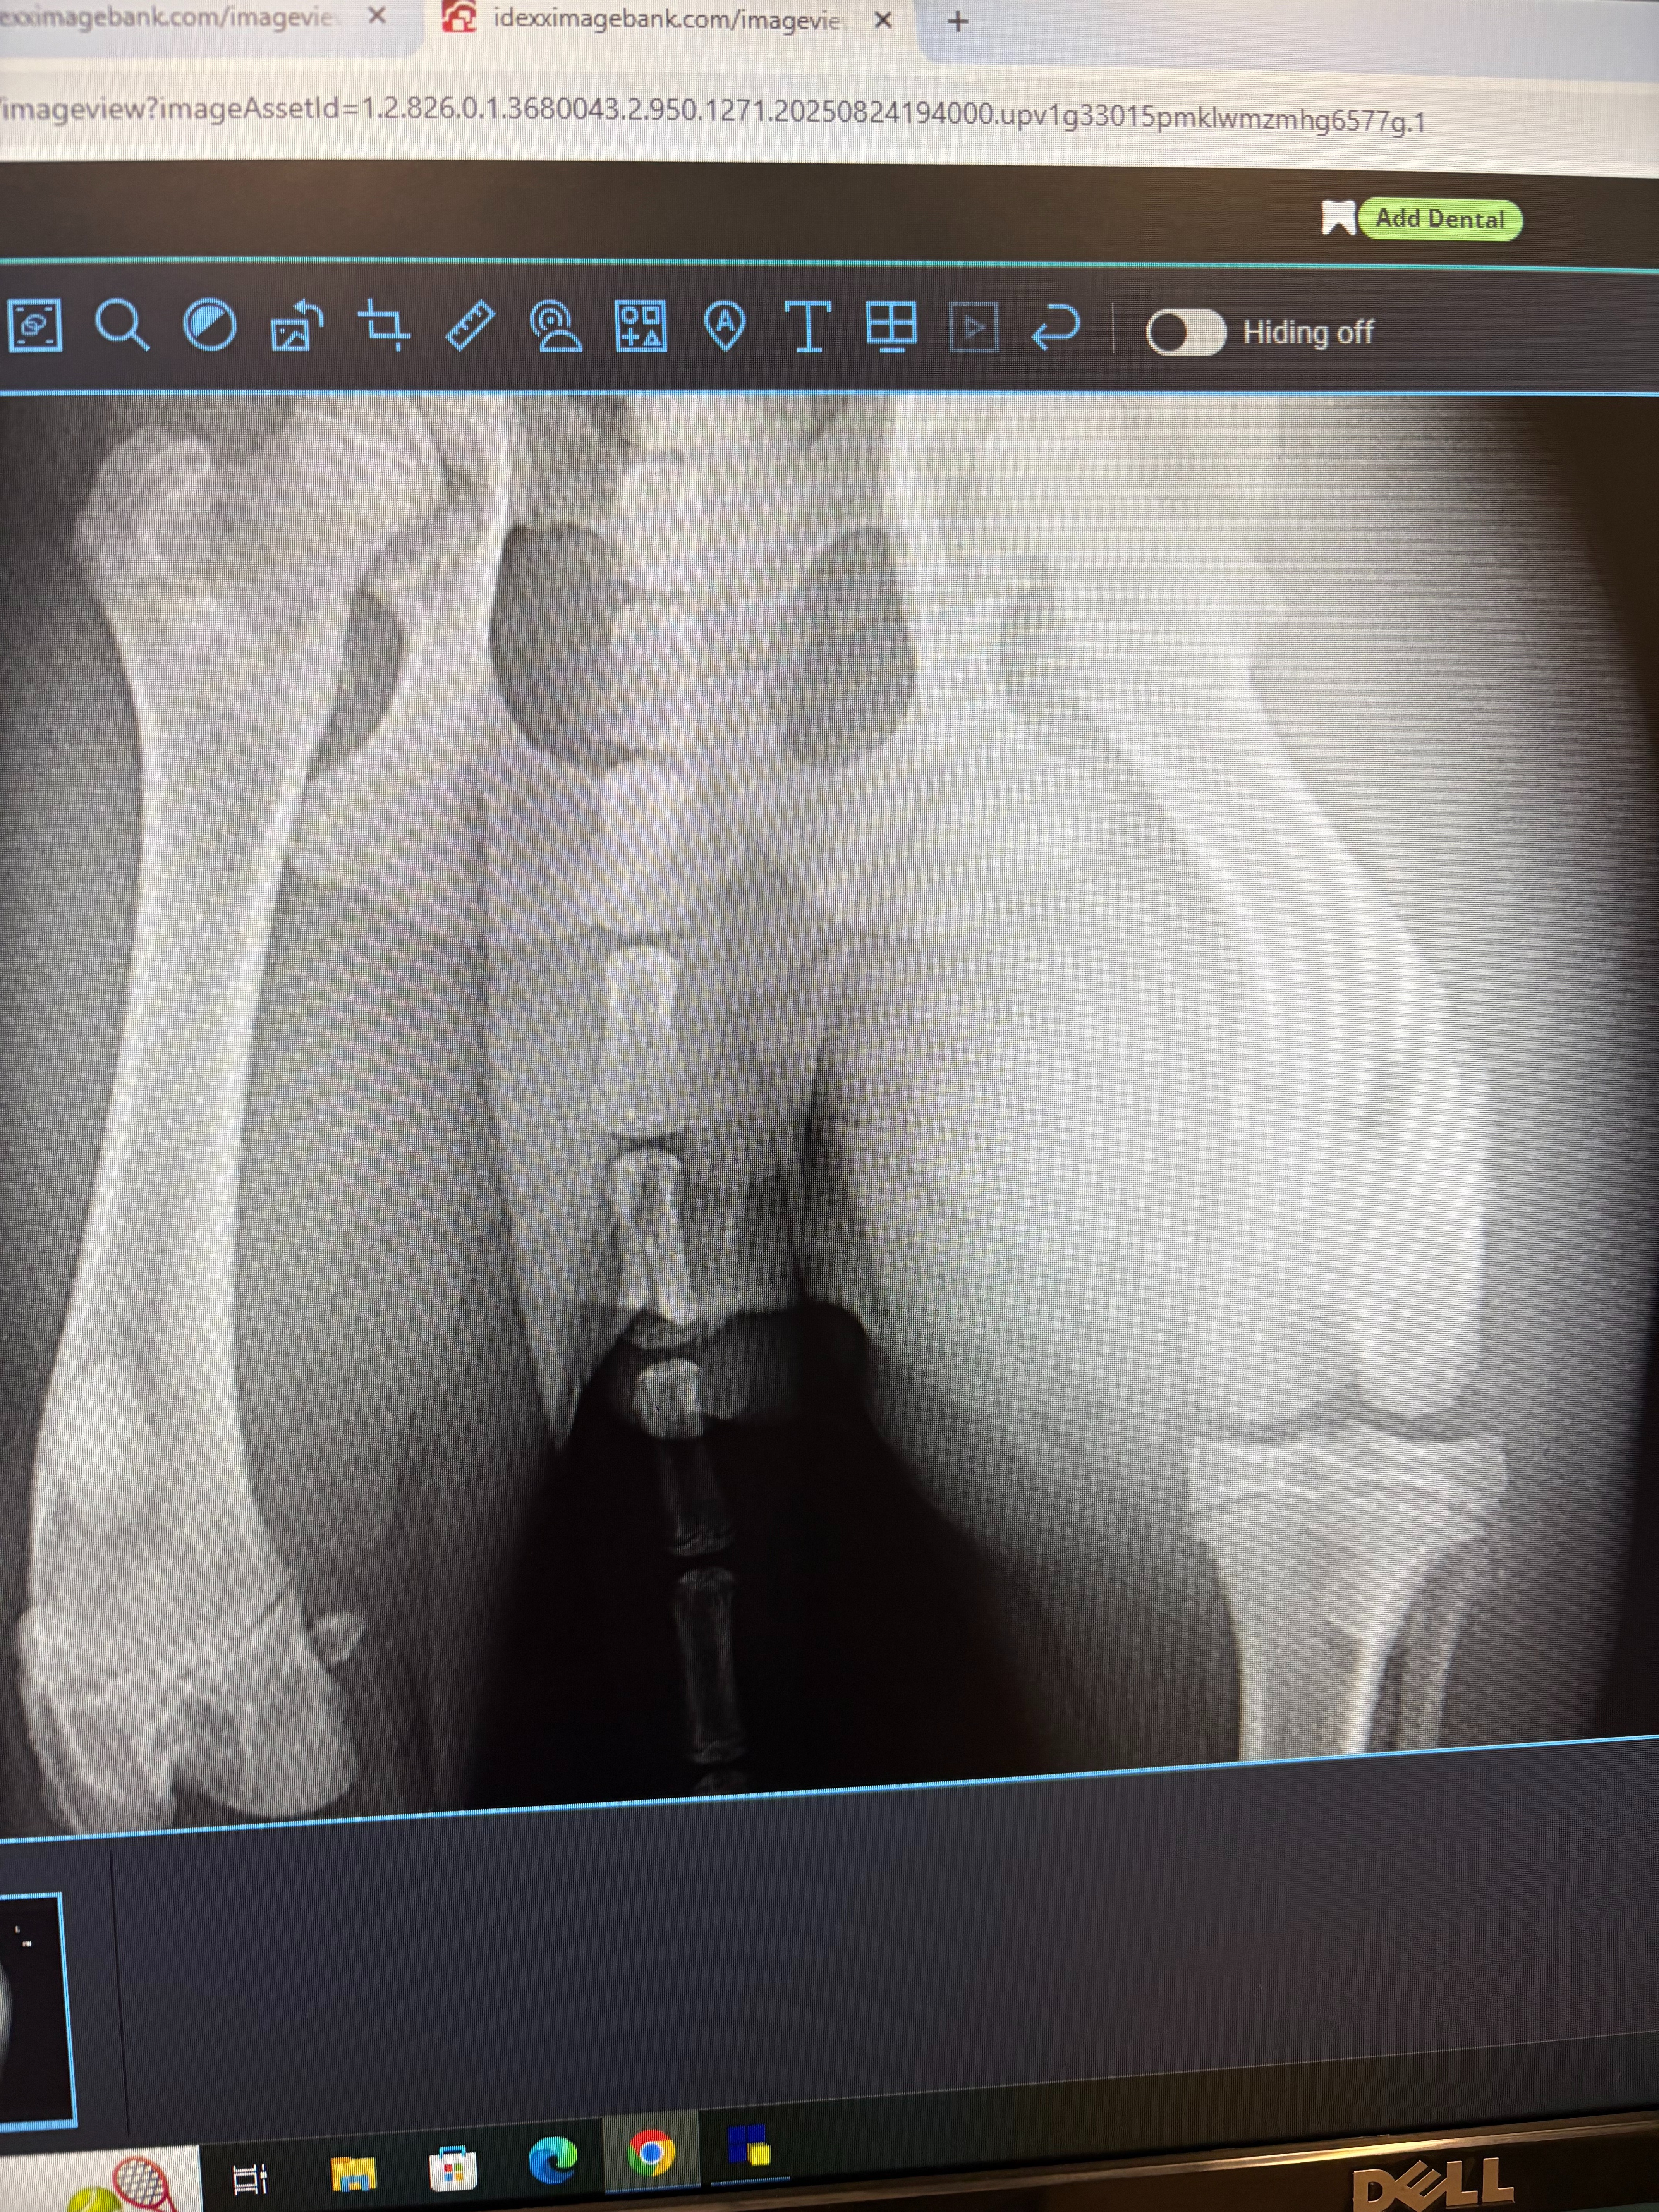

The vet did confirm that he will unfortunately have to have his back leg amputated due to a previous break not healing properly.

We are looking to adopt him into our family and help this little puppy as much as we can, unfortunately amputations are not cheap.